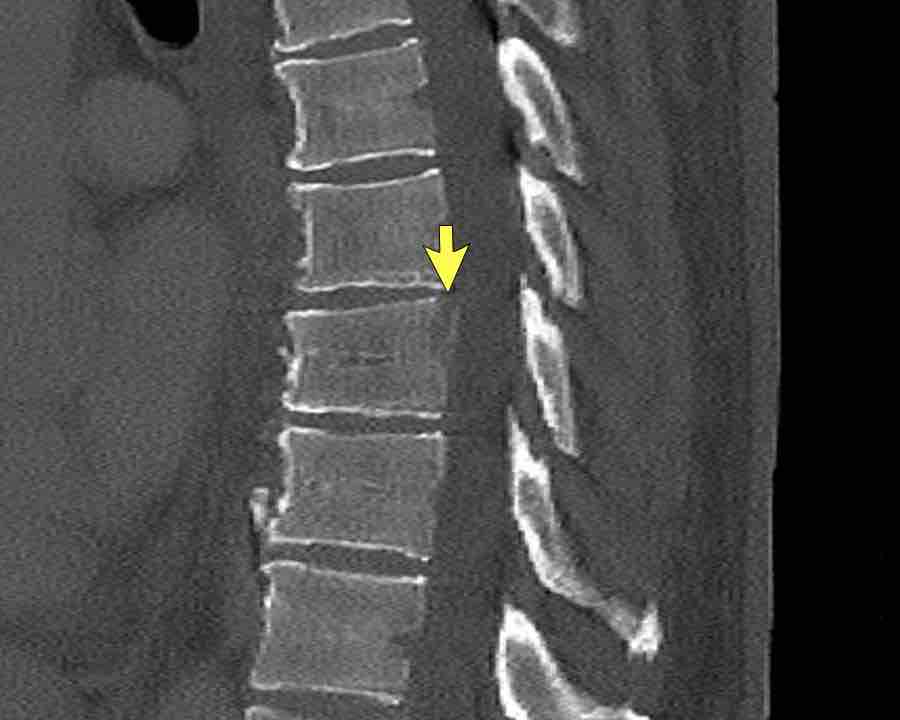

Findings

- Vertical fracture of the posterior border of the vertebral body. It looks a bit odd.

- Again we first have to look for the presence of a type C injury.

- Notice that there is a subtle posterior dislocation of the proximal levels. So this has to be C injury.

Conclusion

Injury type C + A3